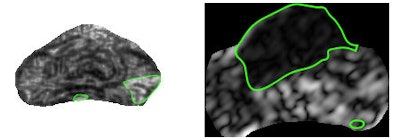

| Sample textural representations found to be highly discriminatory for peripheral zone tumor (left) and central gland tumor (right) show difference in texture with cancer region (green outline) and rest of prostate. |